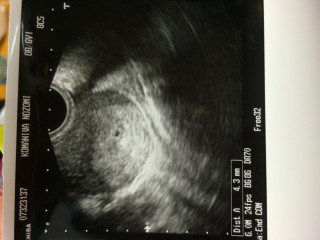

ありました! 胎嚢! 現在5ミリで、順調ですとのことでした◎ まだまだ気は抜けませんが2週間後に心拍確認できるのを心待ちにしています(о´∀`о)

先生がまだ見えませんねーって言ってる時にあっあった!って見つけました(*´・_・`*)先生はあ、ありましたねーごめんなさいねーって言われちゃったけど おめでとうございますと言われ一安心しました!ちょっとずつ実感してきてすごい嬉しい(;;) 来週病院にいくのが楽しみですヽ(o´∀`o)ノ元気に育ちますように☆

これかなー?っていうのが写ってました(´•ω•`)♡ まだまだ小さいけど、頑張ってほしい。 次は2週間後!心臓の音聞こえるといいな~。

初めてエコーで見られて嬉しかった^^ お医者様はここから育っていくかどうかはまだ分からないと仰っていたけれど、無事大きくなってくれるといいな~♡